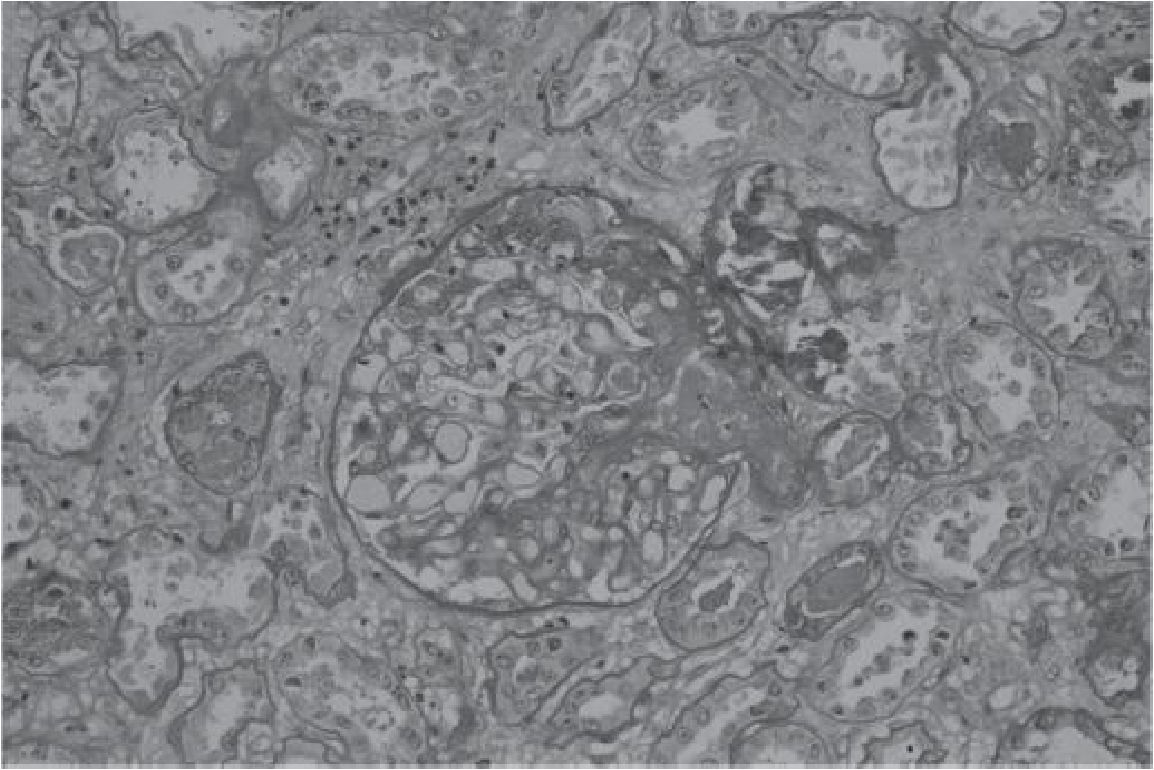

A 51-year-old female with ESRD of unknown etiology received deceased donor KT from a 57-year-old donor. The cold ischemic time was 22 hours. The degree of HLA mismatch was 2 of 6 and the recipient PRA was 3%. The dialysis vintage was 8 years. The immunosuppression included basiliximab induction, tacrolimus, mycophenolate mofetil (MMF) and prednisolone. She had delayed graft function (DGF) requiring hemodialysis for 3 weeks. On 4th week, the kidney function was improved. Urine output increased to about 1000-3000 ml per day and serum creatinine was 2.17 mg/dl. Transplant kidney biopsy at 6th week showed acute tubular necrosis without evidence of rejection. Two months after KT she presented with the change of mental status for a few days. She subsequently had psychomotor retardation, slow speech, myoclonus on both hands followed by generalized tonic-clonic seizure. Antiepileptic drugs were administrated by phenytoin and diazepam intravenously. Serum electrolyte was normal, the platelet count was 48,000 /ml, hemoglobin 10.9 g/dl and peripheral blood smear show schistocyte, polychromasia, and decrease platelet compatible with microangiopathic hemolytic anemia (MAHA) pattern. Tacrolimus level was 6.0 ng/ml. MRI brain showed multifocal symmetric hypersignal FLAIR lesion at bilateral medial thalami, bilateral hypothalami, bilateral optic tract, bilateral periventricular frontal horns and subcortical area compatible with posterior reversible encephalopathy syndrome (PRES) [figure 1]. Serum creatinine rose to 6.49 mg/dL, blood urea nitrogen (BUN) was 65 mg/dL and donor-specific antibody is negative. The diagnosis of TTP/HUS was given. Plasmapheresis was initiated accompany with hemodialysis. Tacrolimus was stopped. Repeated kidney biopsy showed fibrin thrombi, shrinkage of the glomerular tufts, without crescent. The arteries show endothelial swelling with foamy cells and focal intimal arteritis, arterioles show moderate hyaline and fibrin thrombi. The findings are compatible with thrombotic microangiopathy [figure 2]. The peritubular capillaries (PTC) show focal luminal leukocytes (less than 10% of cortical PTC) and the immunop-eroxidase staining for C4d is focally positive (10%). Several weeks after treatments, the neurological symptoms improved, TMA was in remission but required regular hemodialysis.

Figure 2 Renal pathology showed fibrin thombus in the afferent arteriole. The tubules show diffuse injury and necrosis.